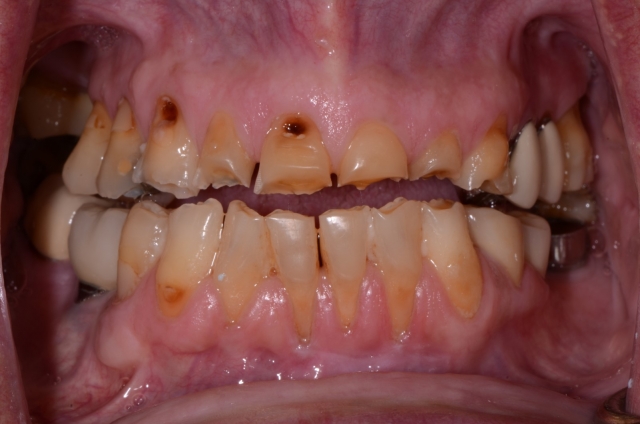

During the oral examination, I recognized that Roger had three of the syndromes we discussed above: extreme worn dentition, xerostomia, and GERD. The damage was extensive and left his dentition in an extremely catastrophic state.

At this point, my job was to educate him as to the true state of his dentition. A patient doesn’t always recognize the gravity of the situation until it’s too late; it becomes our responsibility to inform them and educate them as to the consequences of these conditions.

This is a great time to enlist the skills taught at Spear. The Treatment Planning With Confidence course specifically equips dentists to address these challenges. For example, knowing how to illustrate the patient’s true condition with 35 mm photography is a powerful teaching tool that not only identifies the disease processes but also effectively educates the patient as to their best restorative option.

When we see the syndromes causing a terminal dentition, we see the potential IMFH patient. I say “potential” patient because I believe it’s important to share all treatment options with a patient. Roger, for example, was presented several options, including orthodontic correction and traditional crown and bridge, and it was his choice as to which option best fit his life circumstance.